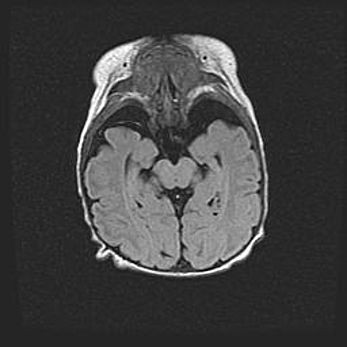

Множественные кисты обоих полушарий головного мозга, наибольшая из них в правой затылочной области. Ассиметричная атрофическая гидроцефалия.

Возраст: 7 месяцев

Вес: 5660 г

Пол: мужской

Окружность головы: 41,5 см

Срок гестации: 28-29 недель

Кисты головного мозга развиваются в результате многоочаговых некрозов вещества мозга и возникают вследствие перенесенной перинатальной инфекции, менингитов, энцефалитов, асфиксии, родовой травмы, расстройств мозгового кровообращения различного генеза. Образованию кист в веществе головного мозга плодов и новорожденных способствуют такие факторы, как высокое содержание в нем воды, недостаточная (или отсутствие) миелинизация и слабая астроглиальная реакция на повреждение.

Кисты могут сочетаться с гидроцефалией и другими поражениями головного мозга.